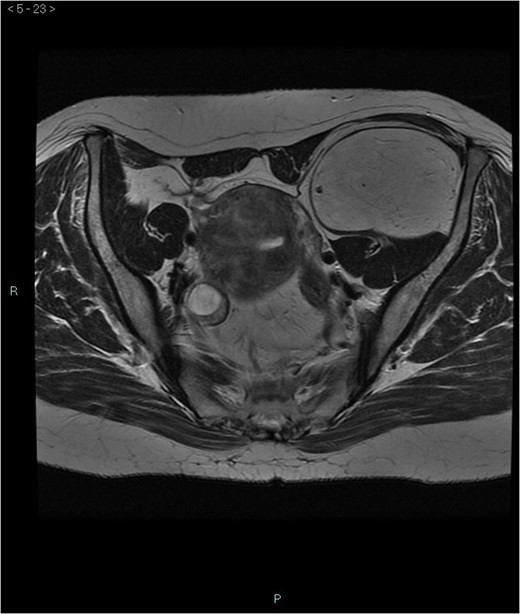

Abdominal hibernoma is a rare slow-growing tumor originating from brown adipose tissue. Due to its rarity, only a few case reports have been published so far. Pelvic localization is anedoctal and preoperative differential diagnosis with other malignancies may be challenging. We present the case of a woman who, due to a lower abdominal pain, underwent an abdominal ultrasonography with diagnosis of a 15 cm hyperechogenous pelvic mass. A subsequent MRI showed a 16 × 5.8 × 7.8 cm3 lesion anterior to the left iliacus muscle, with an intra- and extrapelvic component longitudinally extending from the left anterior superior iliac spine until the lesser trochanter. Surgical resection was performed and final histopathology was consistent with hibernoma. This report emphasizes the necessity to include hibernoma among differential diagnosis when a retroperitoneal abdominal mass is diagnosed and the difficulty to perform preoperatively this diagnosis due to the extreme rarity of these neoplasms.

A 58-year-old woman was evaluated for lower abdominal pain, without additional symptoms. An abdominal ultrasonography revealed the presence of a 15 cm homogenous mass, located in the left pelvic cavity. Subsequent MRI showed a capsulated mass, isointense with the adipose tissue, longitudinally extending from the left inguinal area to the left leg root and located on the medial aspect of the left iliac bone. MRI also revealed within the mass some fibrotic branches containing small blood vessels. No evidence of extracapsular invasion of the surrounding structures was evident (Figs 1–6).

Preoperative differential diagnosis is mainly based on radiologic imaging and is very difficult, because no pathognomonic signs exists for diagnosis of hibernoma; usually CT-scan shows an homogenous lesion, whose density is between subcutaneous fat and skeletal muscle; MRI shows slightly lower signal intensity on T1 weighted spin-echo (T1WSE), marked enhancement and partial fat suppression on short Tau inversion recovery (STIR) and fat-saturated sequences [5].